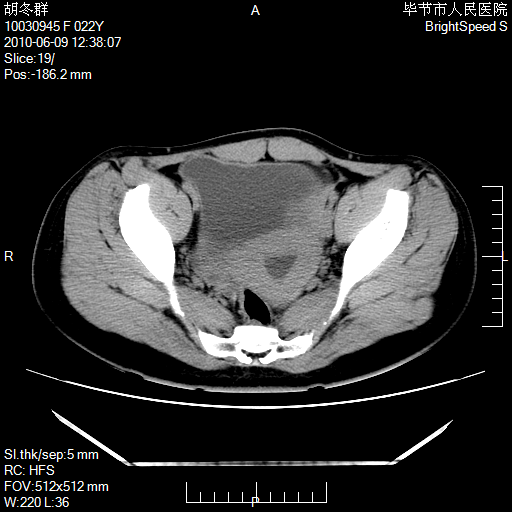

患者23岁,发现腹部包块3月。

左侧卵巢囊腺瘤或囊腺癌

盆腔内囊性占位性病变;考虑左侧卵巢囊腺瘤。

有分隔、壁薄,支持考虑左侧卵巢囊腺瘤。

左侧卵巢浆液性囊腺瘤。

支持考虑左侧卵巢囊腺瘤;宫腔积液。

有分隔、壁薄,支持考虑左侧卵巢囊腺瘤。排尿后,膀胱缩小,由于重力作用,肿块下移就到了膀胱位置,很好理解。